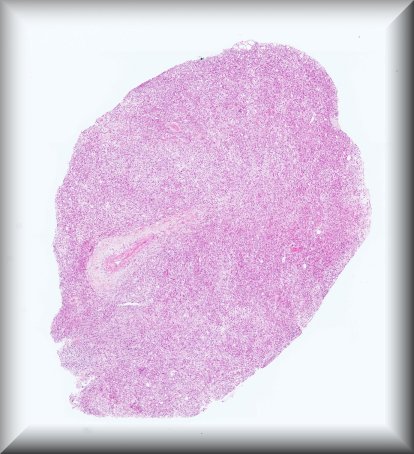

Luis Alfaro (Valencia): Rapidly growing tumour in a 51-year-old male affecting the orbit and involving the eyeball. Extended exanteration was performed, towards the skull and left facial region. Protocol |